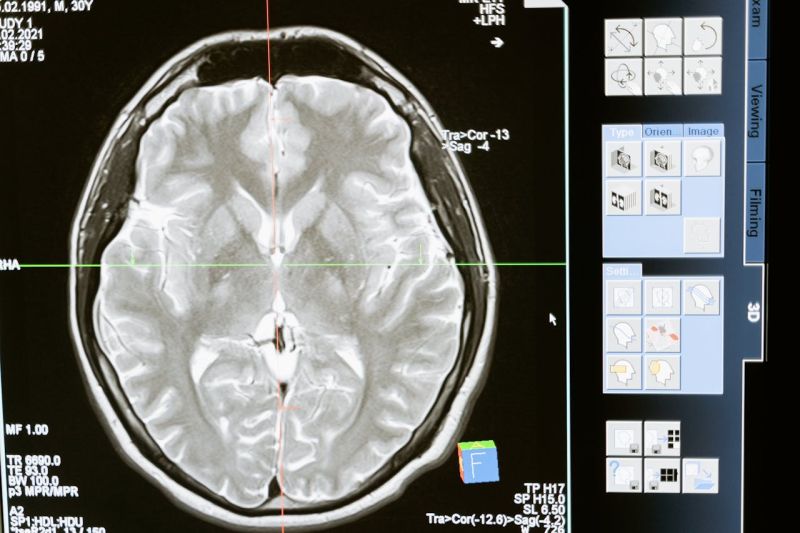

U klinici Magnetna Rezonanca Beograd izvodi se magnetna rezonanca glave uz pomoć savremene opreme i stručnog nadzora lekara. Pregled je bezbolan, bez zračenja i omogućava otkrivanje različitih promena u mozgu i nervnom sistemu.

Magnetna rezonanca (MRI) glave omogućava precizne i detaljne snimke mozga i okolnih struktura bez korišćenja rendgenskog zračenja. Pregled se preporučuje kod jakih ili neuobičajenih glavobolja, vrtoglavice, poremećaja vida i sluha, epileptičnih napada ili sumnje na moždani udar. Takođe se koristi za otkrivanje tumora, promena u krvnim sudovima, upala i degenerativnih oboljenja. Tokom pregleda pacijent leži mirno u aparatu dok uređaj pravi snimke, uz mogućnost primene kontrasta kada je potrebno radi dobijanja jasnijih informacija. Ceo postupak traje od 30 do 60 minuta, bezbolan je i bezbedan, a rezultati se prosleđuju lekaru radi daljeg tumačenja.

Šta magnetna rezonanca može otkriti

• Tumore i ciste na mozgu.

• Moždani udar i krvarenje, uključujući posledice takvih povreda.

• Ožiljke i promene nastale usled povreda glave.

• Demijelinizacijske promene, kao kod multiple skleroze.

• Razvojne anomalije mozga i hidrocefalus (prekomerno nakupljanje moždane tečnosti).

• Infekcije i upale mozga.

• Aneurizme i malformacije krvnih sudova.